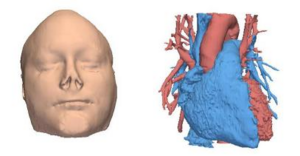

- 3.32 MIDA: A Multimodal Imaging-Based Detailed Anatomical Model of the Human Head and Neck